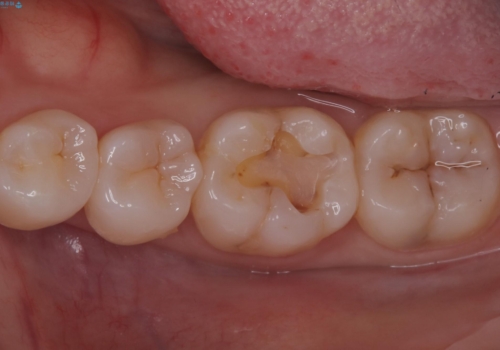

- 主訴:左下の奥歯がなんだか他の歯に比べて青白い気がする。虫歯じゃないか見てほしい。

左下6番目の歯の咬合面で虫歯が進行しており、プラスチックを用いた治療とセラミックを用いた治療を提案し、適合や材料安定性の良いセラミックインレーでのやり替えとなりました。

咬合面のカリエスの場合、CR修復で済ませることが多いですが、CRは経年的に劣化し二次う蝕を引き起こすリスクがあるため適合や経年劣化しにくいセラミックでの治療となりました。